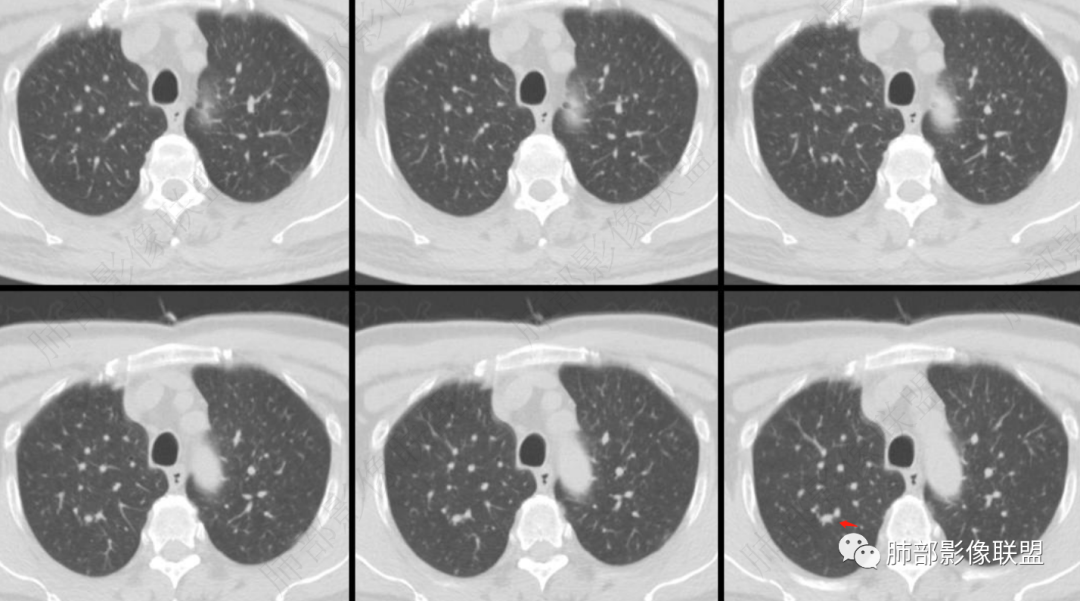

病例资料

右肺上叶尖段实性结节 炎性肉芽肿?增殖灶?

实性结节,形态不规则,与周围血管关系密切,腺癌不排除

右肺上叶血管间不规则实性结节,边界清,分叶,小叶间隔阻挡,考虑腺癌,鉴别炎性肉芽肿

3、右肺上叶不规则实性密度为主结节影,可见浅分叶,边界隐约可辨,界面欠清晰。病灶密度欠均匀,边缘似可见磨玻璃影,未见钙化及卫星灶。

4、矢状位示病灶沿肺动脉长轴走形,边缘较平直;

5、未提供肺门及纵隔影像。肺门及纵隔淋巴结情况未知。

6、综合分析,右肺上叶单发实性小结节,浅分叶,边界隐约可辨,未能明确与支气管关系。病灶边界不够清晰游离(与邻近肺组织多有瓜葛),加之缺乏周边征象,硬化性肺细胞瘤等良性肿瘤可能性较小。

需要鉴别的是炎性病灶(如炎性肉芽肿)与恶性肿瘤。病灶较小,恶性征象不多(小支气管阻塞、深分叶及毛刺、清楚的磨玻璃晕,张力高等等),仓促定性,未免仓促,可以定期复查是否有变化,穿刺活检也可视为积极措施,唯病灶较小,幽深不测,难度较大。

7.注意:1)血管旁实性密度小结节有时易被“瞒天过海”2)不宜轻视任何一个肺部结节。